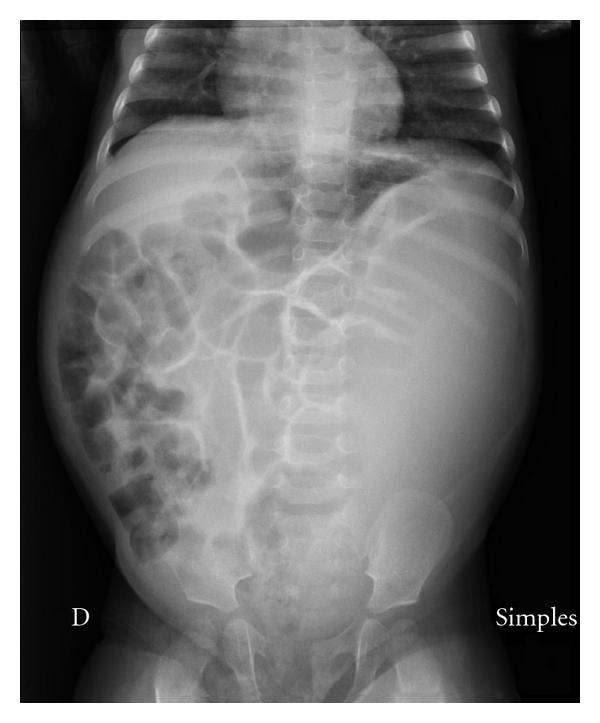

Abdominal compartment syndrome caused by massive pyonephrosis in an infant with primary obstructive megaureter.

The authors report a case of abdominal compartment syndrome caused by massive pyonephrosis in an infant with primary obstructive megaureter successfully treated with emergency surgical decompression.